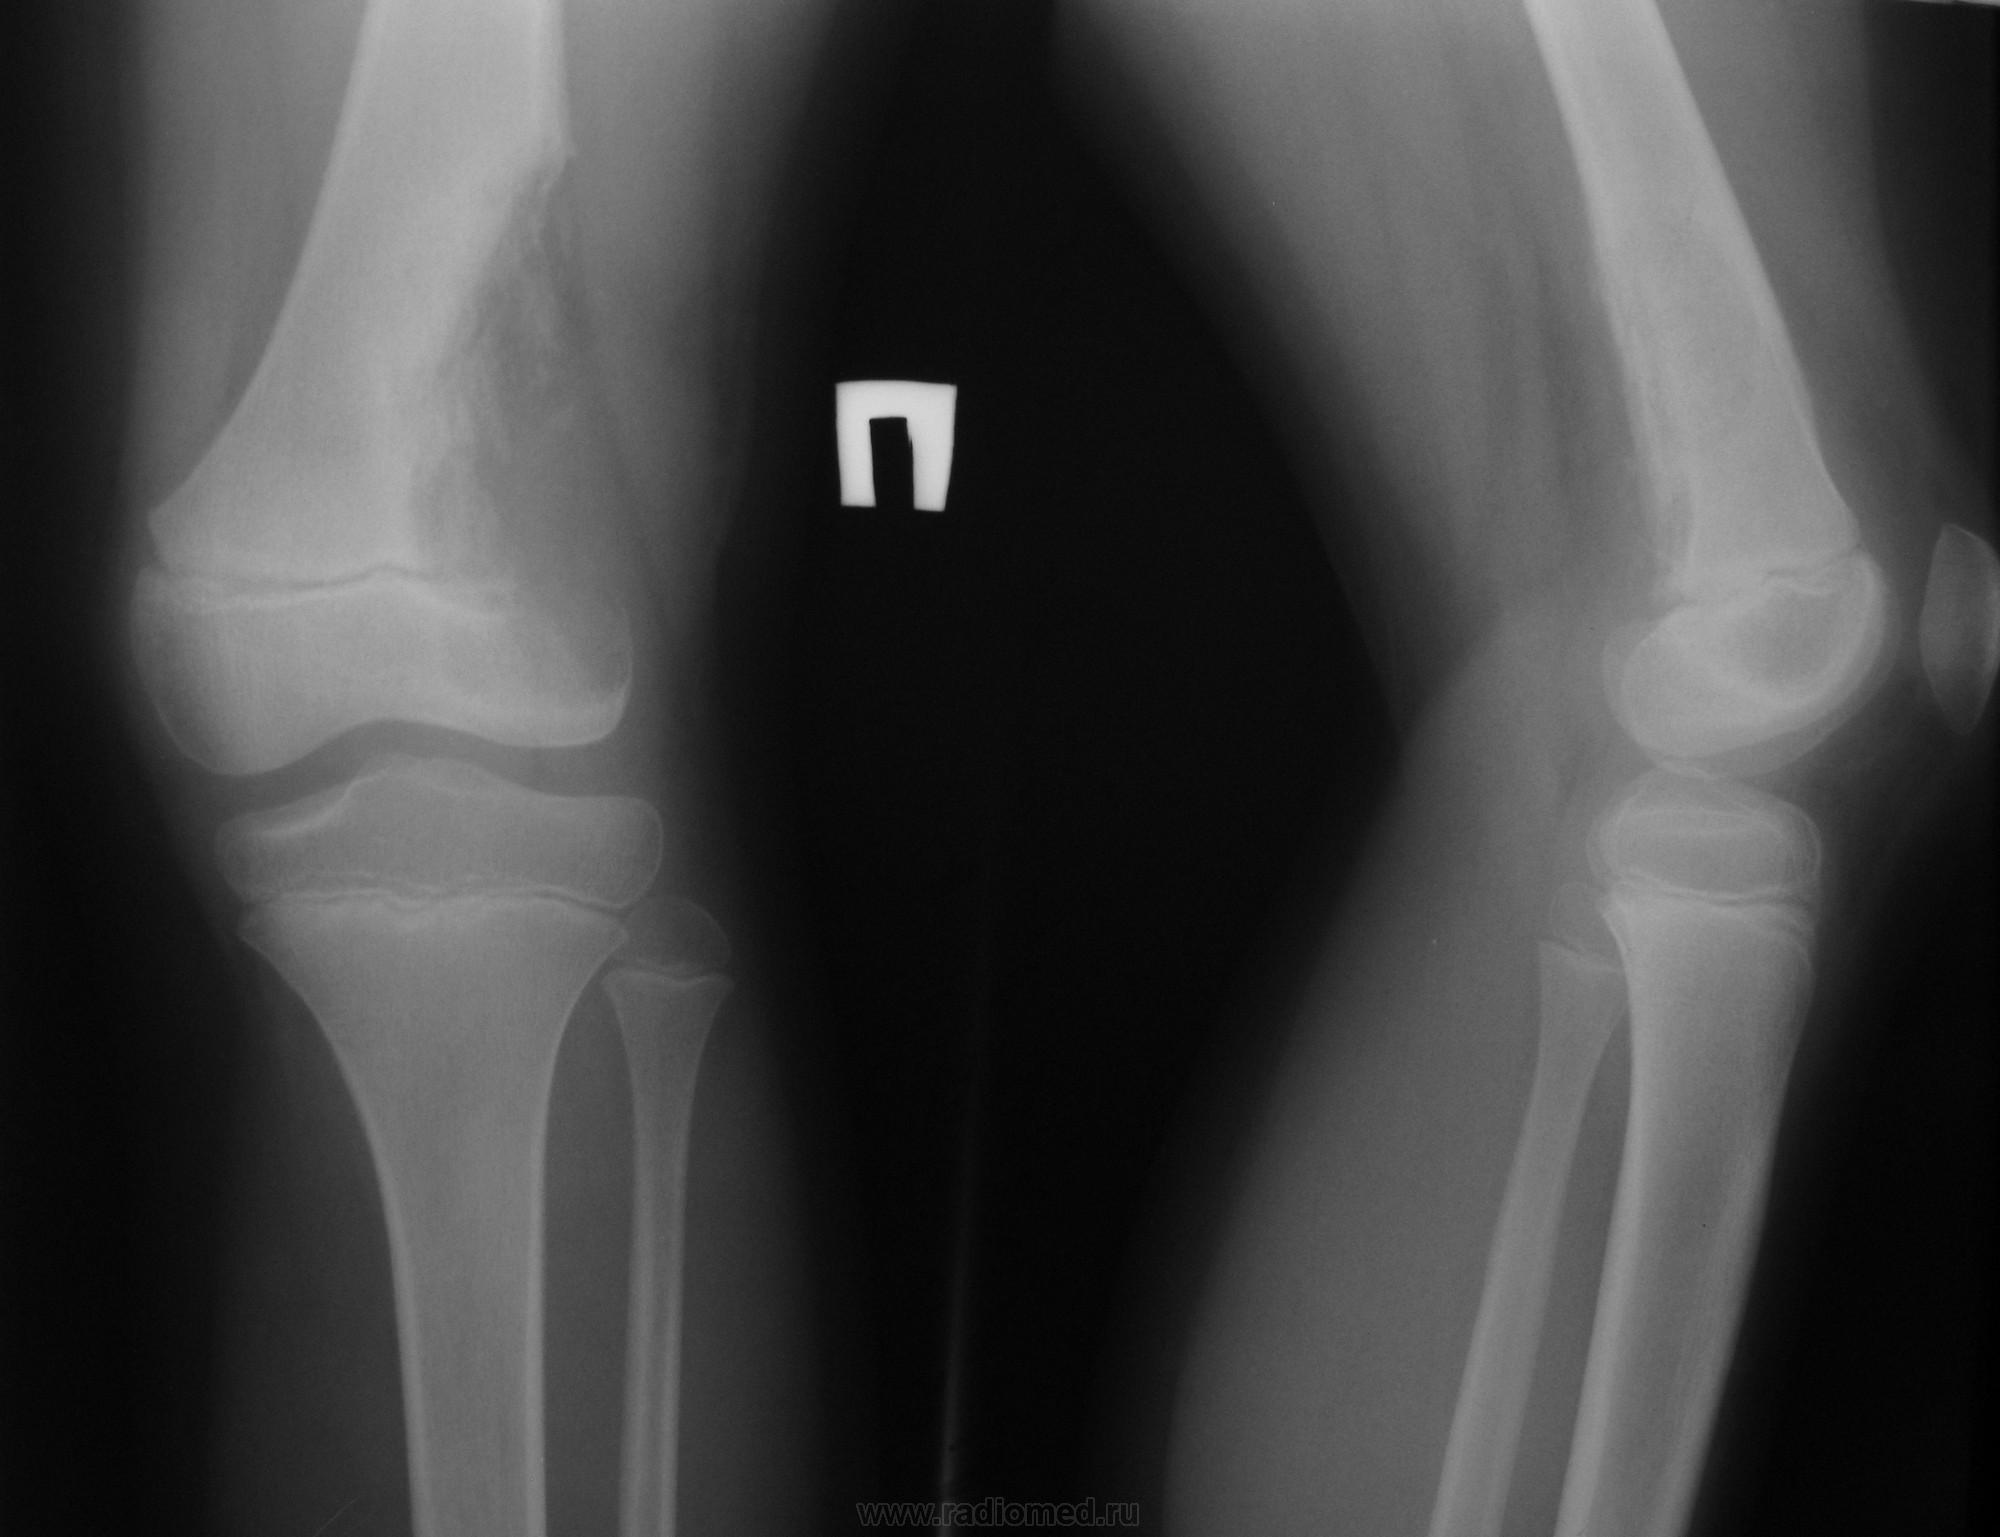

Девочка 6 лет. В течение 2 недель отмечает боли в бедре, ночного компонента болей нет. Однократно повышалась температура тела до фебрильных цифр. Местно: болезненность при пальпации в н/3 бедра, припухлости нет. Дижения в коленном суставе в полном объёме. Ходит, слегка прихрамывая.

Выполнили рентгенограммы. Компьютерный томограф сломан уже несколько месяцев с необнадёживающей перспективой починки в ближайшее время.

1. Массивный литический очаг - остеосаркома/Юинг? Но: отсутствие клиники злокачественной опухоли? Отсутствие периостоза, да и патологический процесс распространяется через зону роста, что для сарком/Юинга нехарактерно.

2. Остеомиелит? Но - где температура, отёк и все остальные сопутствующие признаки гнойного процесса? При такой выраженной деструкции они должны быть также крайне выраженными.

3. Туберкулёз? Вроде бы всё сходится. И лизис, и распространение через бессосудистую зону. Но уверенности нет.

Рентгенологически — остеолитический эксцентрично расположенный очаг без признаков обызвествления и чётких границ; периостальная реакция обнаруживается редко; обычно разрушение кортикальной пластинки и распространение опухоли в мягкие ткани.